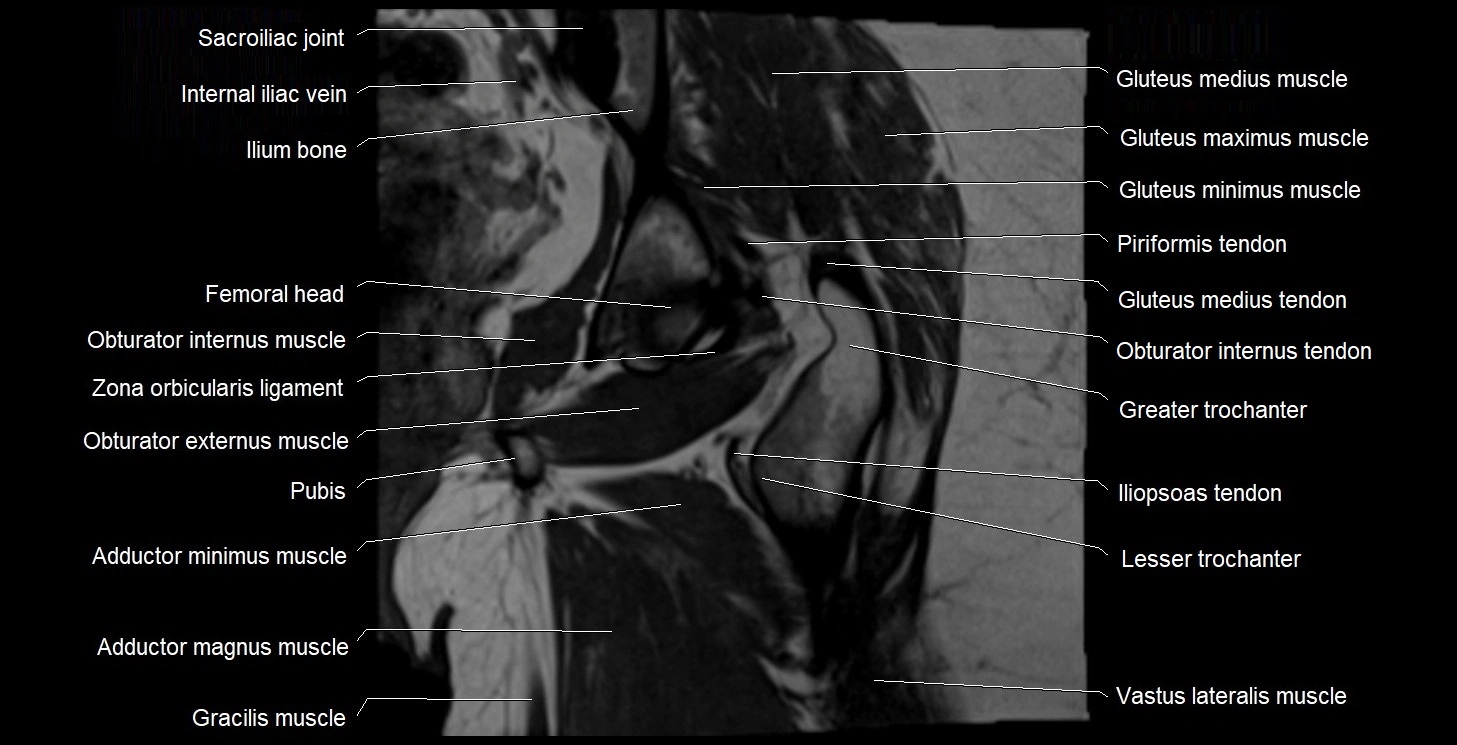

- Sacroiliac joint

- Ilium bone

- Head of femur

- Obturator internus muscle

- Zona orbicularis ligament

- Obturator externus muscle

- Body of pubis

- Adductor minimus muscle

- Adductor magnus muscle

- Gracilis muscle

- Gluteus medius muscle

- Gluteus minimus muscle

- Gluteus maximus muscle

- Gluteus medius tendon

- Obturator internus tendon

- Greater trochanter

- Iliopsoas tendon

- Lesser trochanter

- Vastus lateralis muscle